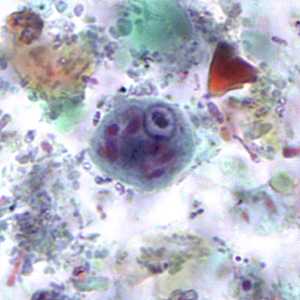

E. coli cysts stained with trichrome.

Figure A: Immature cyst of E. coli, stained with trichrome. Notice the presence of only two nuclei, and a large glycogen vacuole.

Figure B: Mature cyst of E. coli, stained with trichrome. Five nuclei are visible in this focal plane.

Figure C: Mature cyst of E. coli, stained with trichrome. In this specimen, at least five nuclei are visible in the shown focal plane.

Figure D: Mature cyst of E. coli, stained with trichrome. In this specimen, at least five nuclei are visible in the shown focal plane.

Figure E: Mature cyst of E. coli, stained with trichrome. This figure and Figure F represent the same cyst shown in two different focal planes. Eight nuclei can be seen between the two focal planes. Also, above the cyst in this figure, a trophozoite of Endolimax nana can be seen.

Figure F: Mature cyst of E. coli, stained with trichrome. This figure and Figure E represent the same cyst shown in two different focal planes. Eight nuclei can be seen between the two focal planes.